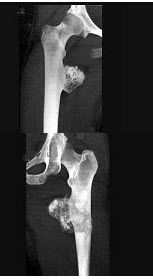

49、单项选择题

男,60岁,左股骨痛1年余,结合图像,最可能的诊断是()

A.骨纤维异常增殖症

B.Paget病

C.髋关节结核

D.股骨头缺血坏死

E.化脓性骨髓炎